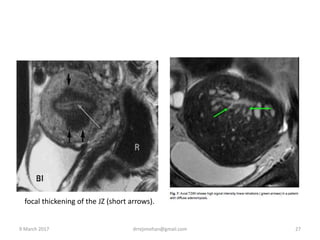

focal thickening of the JZ (short arrows).